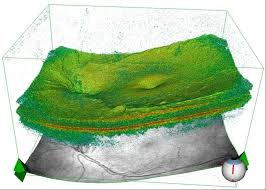

OCT..the diagnostic tool for diseases of retina

Optical coherence tomography (OCT) is a non-invasive imaging test. OCT uses light waves to take cross-section pictures of your retina.

With OCT, your ophthalmologist can see each of the retina’s distinctive layers. This allows your ophthalmologist to map and measure their thickness. These measurements help with diagnosis. They also provide treatment guidance for glaucoma and diseases of the retina. These retinal diseases include age-related macular degeneration (AMD) and diabetic eye disease,vascular occlusions as discussed above.